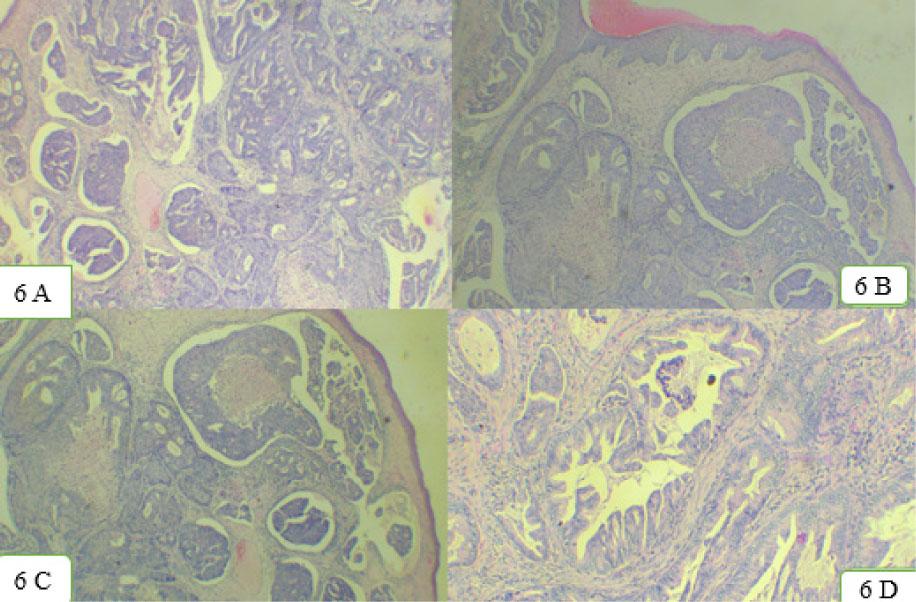

Figure 6:

Immunohistochemical and Histopathological features of Intestinal Sinonasal Adenocarcinoma_

| IMMUNOHISTOCHEMICAL MARKERS | HISTOPATHOLOGICAL FEATURES |

|---|---|

| Pancytokeratin and CK7: Indicates keratin producing cells | Tubulo-glandular architecture: Consists of tubules and glands |

| MUC2: Mucin protein | Papillary appearance: Papillary elements |

| CK20, CDX2, and SATB2: Negative inITAC | Colonic resemblance: Histopathological resemblance to colonic adenocarcinoma |

| S100 protein, SOX10, and Discovered on GIST-1(DOG1): Indicatesneuroendocrine differentiation | Signet ring cell morphology |

| Carcinoembryonic Antigen (CEA): Weak expression than colonicadenocarcinoma | Goblet cells : Present in papillary and mucinous subtypes |

| Chromogranin: Numerous Chromogranin positive cells compared tocolonic adenocarcinoma | Positive mitotic activity |